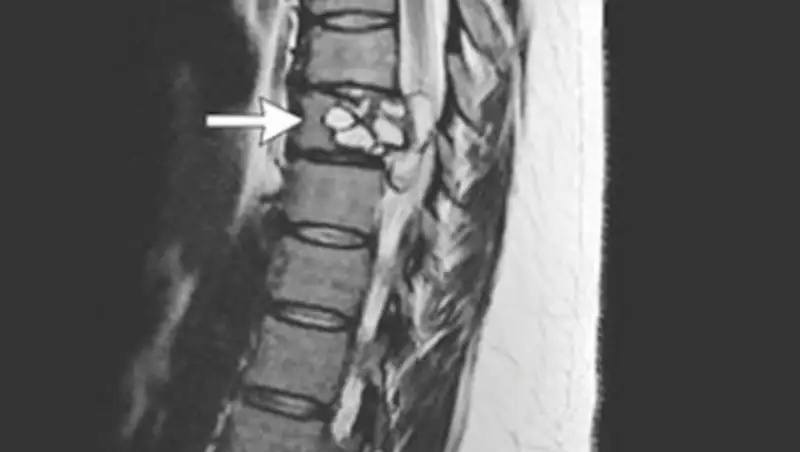

Женщина лежит в больнице, состояние средней степени тяжести, ушиб грудной клетки, перелом позвоночника, получает всю необходимую медицинскую помощь, - сообщили в Управлении здравоохранения Карагандинской области.